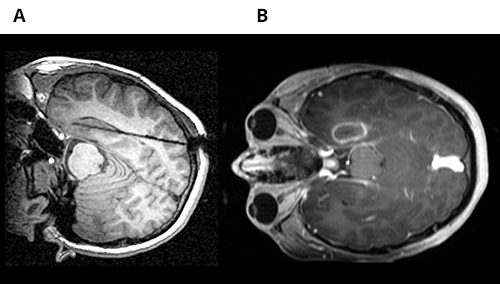

In a 14-year-old patient who underwent SEEG exploration, epileptogenic focus was identified in the left mesial temporal region. MRI-guided laser interstitial thermal therapy was used for the treatment of epileptogenic focus. A) Axial MRI view demonstrates the location where laser probe was placed B) Axial MRI view indicates the location of thermal ablation.